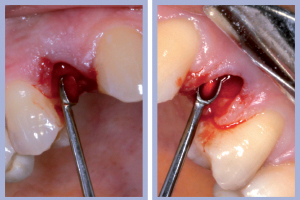

- Figg. 4a, b – Scollamento

- Figg. 5a, b – Estrazione dei canini da latte

- Figg. 6a, b – Estrazione dei canini da latte

- Figg. 7a, b – Toilette chirurgica

- Figg. 8a, b – Mappatura alveolare tramite sonda parodontale